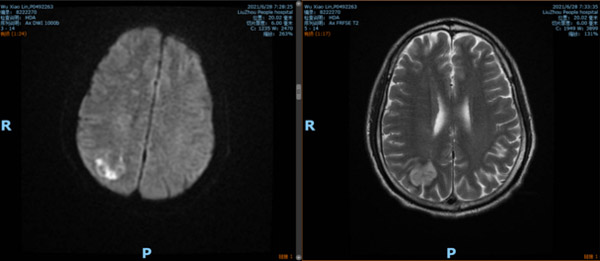

一个月前,在我院内分泌科住院的糖尿病患者吴某出现左侧手脚无力的症状,且越发严重,经MRI(磁共振)检查,诊断脑梗死,右侧颈内动脉颅内部位闭塞,随即转入神经内科进行治疗。

患者年纪较轻,右侧大脑半球缺血严重,有开通闭塞血管的指征,恢复脑组织正常供血。但手术也存在一定风险,首先,患者此次发病不仅有脑细胞缺血坏死,而且由于缺血严重,颅内血管也出现缺血损伤,部分血液渗入脑梗死部位,形成出血转化,如果这个时候把血管开通,出血的风险很高。其次,由于被斑块完全堵塞的颅内血管很细,仅仅有2.5mm,再加上血管壁很薄,使得手术的难度激增,施术者的手在术中发生哪怕微微一点抖动,都有可能造成扩张血管破裂,造成致命的后果,这对于施术者而言,在心理和技术上,都是一种严峻的考验。

经过谨慎评估,先给患者药物治疗,待血管修复后择期开通闭塞血管。在患者进行药物治疗的一个月时间内,高文每天都惦记着这件事儿,细致准备,反复演练,通过高分辨率磁共振结果分析血管斑块,进行评估。同样的步骤在脑海中不知道重复了几十遍,他经常失眠,眼睛一闭就回想起手术的细节,如同在刀尖上行走,容不得半点闪失。